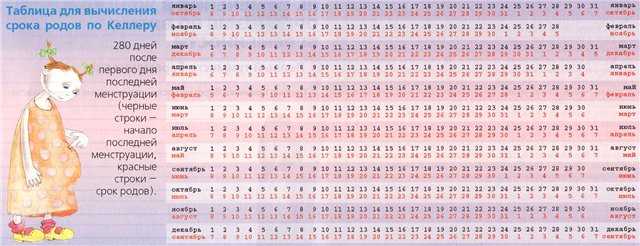

Акушерские недели беременности: особенности и расчёт сроков

Раздел: Идеи и советы